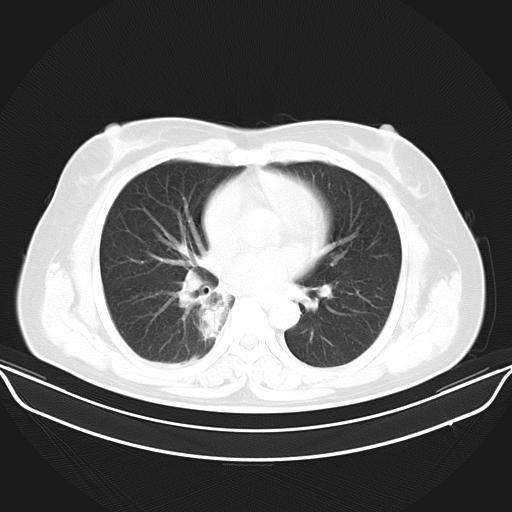

标题: CT22224:肺部肿块

f,48,主因咳嗽咳血来我院检查,无发热。

1)右肺下叶背段团块状软组织密度影;建议抗炎治疗后复查排除肿瘤性病变。2)右侧少量胸腔积液。

胸膜下脂肪影存在,考虑炎性假瘤,建议治疗后复查.

谈一谈个人的看法:机器性能应该不错,可惜扫描方法不太正确,即没有及时薄层扫描图像,也没有增强检查,这样的检查方法不正确的图片拿来研究只能是猜一猜:右肺下叶阻塞性改变,建议进一步检查删除肺癌。

支气管镜检查未见异性细胞,抗炎治疗20天,肿块明显缩小。